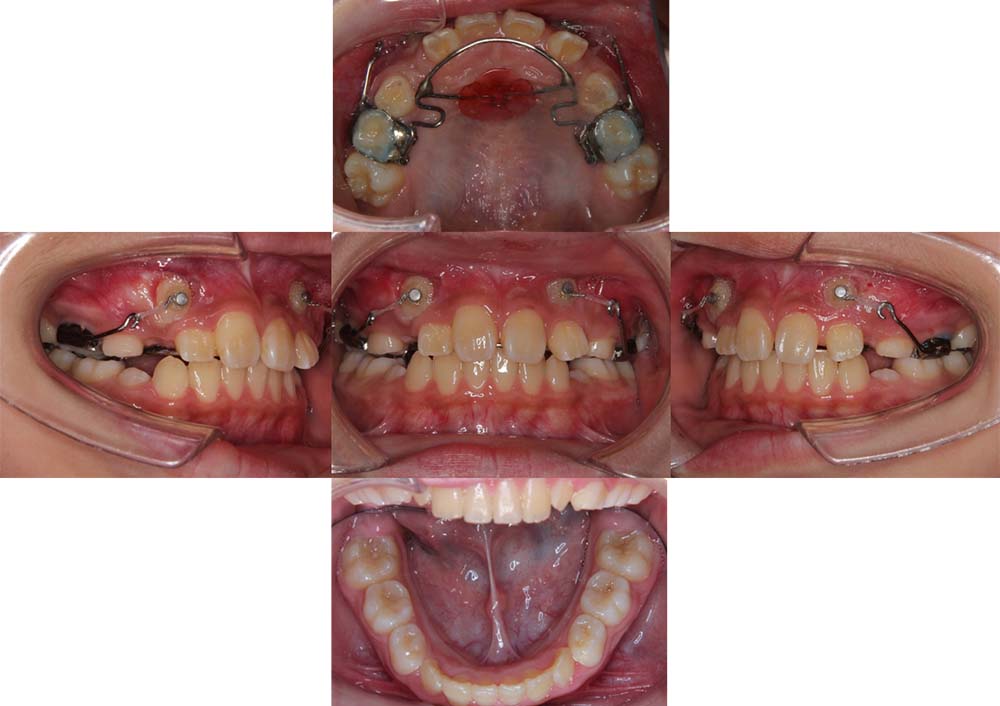

症例13

| 主訴 | 前歯が反対に噛んでいる |

| 診断名あるいは主な症状 | 反対咬合、上顎左側第一大臼歯の半埋伏 |

| 年齢/性別 | 8歳・男児 |

| 矯正ステージ | 子どもの矯正治療 |

| 治療方法 | セクショナルアーチ |

| 抜歯部位/抜歯有無 | – |

| 治療内容 | 部分的なワイヤーにて反対咬合の改善と上顎左側第一大臼歯の萌出誘導。その後は成長と生え変わりの定期的なチェックを行った。 |

| 費用 | 30万円程度(2025.10での料金となります。) |

| 治療期間 | 2年0ヶ月 |

| 主なリスク・副作用 | 痛み、歯根吸収、歯肉退縮、虫歯、後戻り |